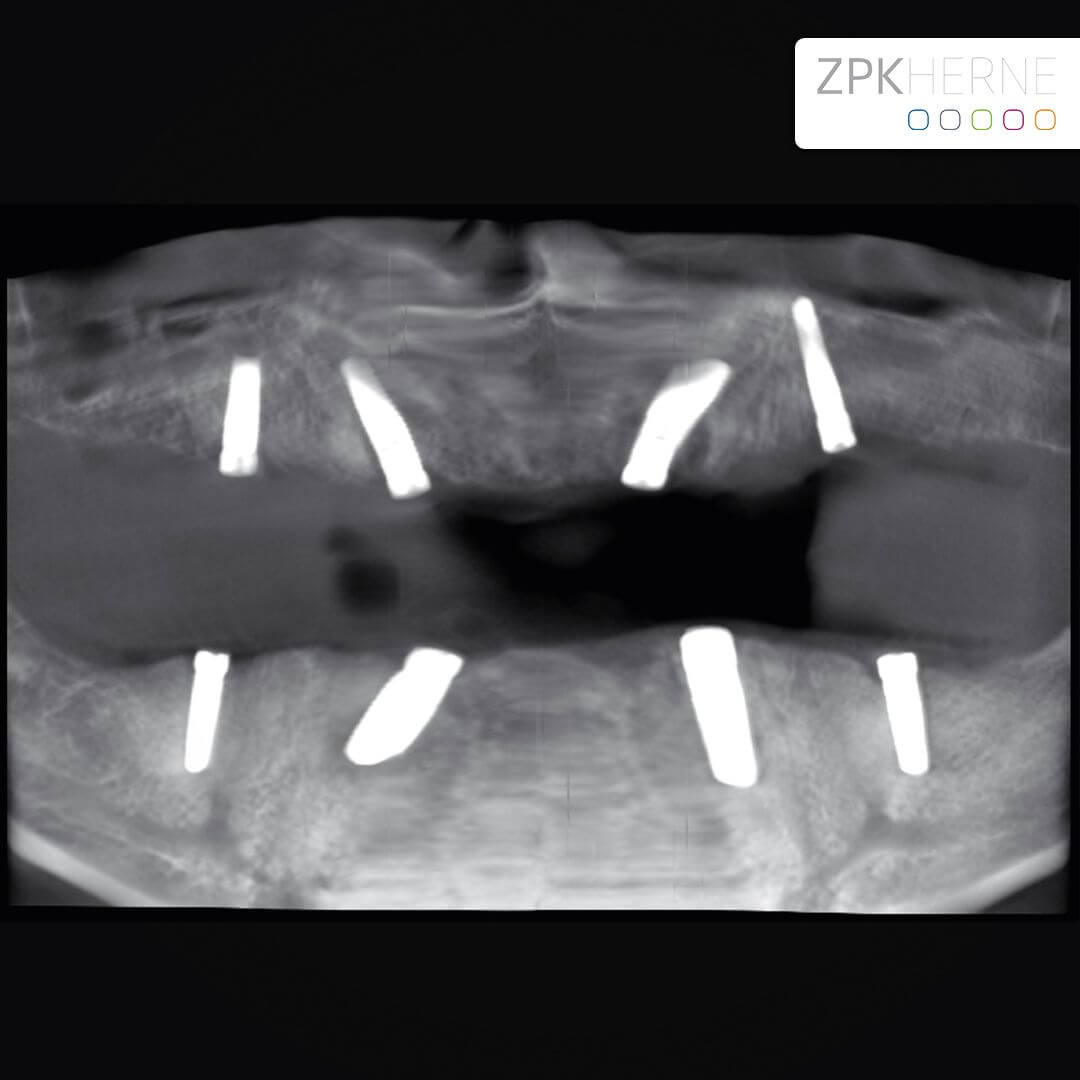

Herzstück des All-on-4 / 6 – Behandlungskonzepts mit Camfour™ ist die aufwendige 3D-basierte Diagnostik. Diese findet im Vorfeld der eigentlichen Zahnimplantation statt. Mit Hilfe von dreidimensionalen DVT-Röntgenaufnahmen und der hochmodernen SIMPLANT®-Software macht sich unser Experte für Implantologie, Dr. Mintert ein detailgenaues Bild von Ihrem Kiefer. Dabei interessieren ihn nicht nur das verfügbare Knochenvolumen, sondern auch die empfindlichen Strukturen des Kiefers, die Knochenqualität und der umliegenden Bereiche. Hierzu gehört neben der Kieferhöhle auch Ihr Unterkiefernerv, auf den wir beim Implantationsvorgang besonders achtgeben müssen. Mithilfe der 3D-Diagnostik kann der Zahnarzt auch feststellen, ob All-on-four/six überhaupt für Sie geeignet ist.

implantat unterkiefer 3d

3d Diagnostik Röntgenbild

Unter Einsatz der SIMPLANT® Planungssoftware kann der Implantolgoe die optimalen Implantatpositionen vorab am Computer planen, wobei sämtliche Planungsdaten anschließend in die Herstellung einer individuellen Bohrschablone einfließen. Die Bohrschablone ermöglicht ein punktgenaues, schonendes Einsetzen der Implantate an den zuvor geplanten Positionen, minimiert das Verletzungsrisiko und beschleunigt letztendlich die Heilung.

Das Behandlung mit Camfour™ sieht 4-6 Implantate je Zahnbogen vor. Meist reichen jedoch 4 Implantate aus. Die speziell für diesen Zweck ausgelegten Zahnimplantate werden mit einem Winkel von bis zu 45° in den Knochen eingebracht. Durch die geneigten Implantate ist der Spezialist für Implantologie unabhängiger vom noch vorhandenen Knochenvolumen und kann ohne einen vorherigen Knochenaufbau implantieren. Wichtig ist, dass die Zahnimplantate bereit unmittelbar nach Einsetzen stabil im Kieferknochen sitzen. Dies wird durch das spezielle All-on-4 ® / All-on-6 ®- Implantationsverfahren sichergestellt. Eine hohe „Primärstabilität“ der Implantate ist die wichtigste Grundvoraussetzung für eine Sofortversorgung mit Zahnersatz noch am gleichen Tag.

Bevor an einen operativen Eingriff gedacht werden kann, stehen als erstes Röntgenbilder mithilfe der Digitalen Volumentomographie auf dem Programm. Hier sind die Überreste in Ober-und Unterkiefer gut zu sehen, vor allem aber die Positionen der abgebrochenen Zahnwurzeln. Auf Basis der Bilder können die Positionen für die insgesamt 8 Implantate auf den Millimeter genau geplant werden: Unser Patient wird jeweils 4 Implantate im Ober-und Unterkiefer erhalten, die im Nachgang jeweils mit einem festsitzenden Zahnersatz versorgt werden. Die Einheilphase dauert zwischen 4 und 6 Monate, prognostiziert Dr. Mintert, der Spezialist für Implantate in der ZPK Herne.

Röntgenbild Kiefer - vor OP

Implantatplanung - Oberkiefer - All-on-Four Konzept

Implantatplanung - Unterkiefer - All-on-Four Konzept